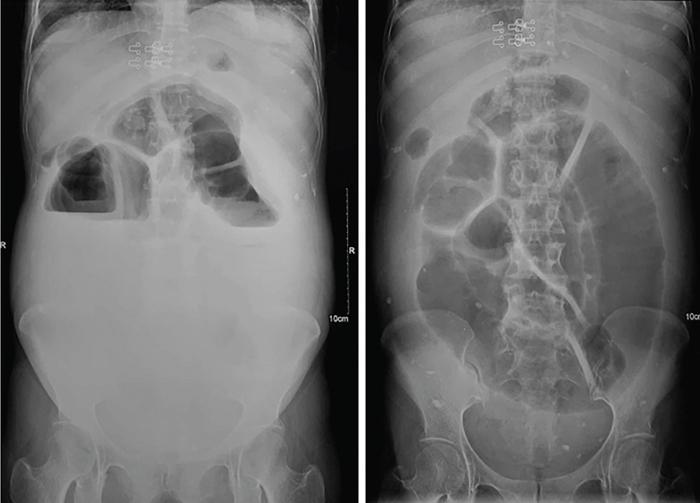

SMALL BOWEL IMAGING Poonam Narang, Himanshu Gupta The small bowel is a long tubular hollow abdominal viscus thrown into intricate folds and loops and packed into the abdominal cavity. It is approximately 5–7 m in length and extends from the gastric pylorus up to the ileo-caecal valve. It is anatomically divided into three parts: duodenum (meaning ‘in twelves’ as its length is roughly equal to the width of 12 fingers), jejunum (meaning ‘fasting’ as it was usually found empty after death) and ileum. The duodenum measures 20–25 cm in length and extends from gastric pylorus to the ligament of Trietz. It is a fixed ‘C’-shaped structure that cradles pancreatic head in its concavity. First part of the duodenum is a triangular conical structure with its base communicating with gastric antrum. Its apex points to the right and cranially, in close apposition with the gall bladder and the under surface of the liver. Second part of duodenum is almost vertical, lying in the right paravertebral gutter. The common bile duct courses obliquely posterior to it and drains at a papilla at its medial wall (the Ampula of Vater), after joining with the main pancreatic duct. Third part is horizontal, crossing the midline between the superior mesenteric artery (SMA) and aorta from right to left, caudal to pancreatic neck. Fourth part is again almost vertical, ascending left of the spine almost to the level of duodenal bulb and transitions to jejunum at duodenojejunal (DJ) flexure. Duodenum is mostly a retroperitoneal structure while the rest of the small bowel acquires a mesentery at the DJ flexure. The jejunum and ileum are intraperitoneal structures, suspended in the abdominal cavity from the posterior abdominal wall by the free end of their ‘fan-shaped’ mesentery and are thus relatively mobile. Though considered a part of small bowel, duodenum differs from the rest of the small bowel in structure as well as function. Plethora of the diseases that affect duodenum are distinct. Peptic ulcer disease affecting the first part does not affect the rest of the small bowel. Most other diseases affecting the duodenum arise from the surrounding structures like pancreas, gall bladder, bile duct, liver and the hepatic flexure of colon. Hence, on imaging, duodenal abnormalities should prompt a search for pathologies of the surrounding organs. While duodenum is structurally a distinct segment, the structural transition from jejunum to ileum is seamless, with no external demarcating point. Histologically, and also on imaging, all three segments have clear identities. Their mucosal lining, folds and presence of submucosal lymphoid follicles are allocated in accordance with their specific functions. Jejunal loops occupy left hemiabdomen and ileal loops, with ileo-caecal junction, lie in the right lower abdomen. Jejunum is about two-fifths of the length of the small bowel, and the ilium forms the rest of the three-fifths of the entire 5–7 m. ‘Terminal ileum’ is a term arbitrarily but commonly used in clinical practice to denote the portion of ileum just proximal to ileo-caecal junction harbouring abundant lymphoid tissue in its walls and playing host to a number of pathologies. At ileo-caecal junction, the ileum joins the caecum obliquely. A valve-like mucosal fold regulates the flow of digested food into the colon and prevents its reflux back. Its efficiency in preventing reflux is quite inconsistent in a large percentage of subjects. The arterial supply of the duodenum is by the branches of hepatic artery (branch of Celiac Axis artery), till the proximal half of second segment (marked by the Ampula of Vater); and by branches of the superior mesenteric artery beyond that point. Duodenal branches of respective superior and inferior pancreatico-duodenal arteries make an arcade along the medial margin of duodenum in the pancreatico-duodenal groove. The rest of the small bowel is supplied by the superior mesenteric artery and its branches while venous drainage is via superior mesenteric vein and its tributaries. These vessels traverse the mesentery, between the twofolds of the peritoneum from the posterior abdominal wall to reach the small bowel forming multiple arcades of vessels within the mesentery. Straight arteries, called the Vasa Recta, arise from the terminal arcade and enter the bowel wall, along its mesenteric border. Disease processes involving the specific artery affects the respective bowel segment that it supplies. Ischaemia, infarction and haemorrhage can be attributed to and localized correctly based on the relevant vascular anatomy. Inflammatory diseases cause engorgement of Vasa recta; and at times, identifying them as a lead point, one is able to localize the involved bowel segment correctly. Vascular ischaemia affects the antimesenteric part of the bowel earlier in the course of the disease. Therapeutic procedures too can be appropriately planned based on the vascular territory of the affected bowel segment. The mesentery forms a fan-shaped suspensory support, tethering the small bowel to the posterior abdominal wall, along a line running obliquely from ligament of Trietz (in LUQ) to ileo-caecal junction close to superior part of right sacro-iliac joint (in RLQ). This ‘root of mesentery’ averages about 15–20 cm in length. It is closely wrapped around small bowel loops and merges with the serosa. All lymphatic and vascular channels supplying to and draining from the small bowel traverse within the mesentery. Thus, pathology originating in one often affects the other by contiguity, haemodynamic alteration or haemo-lymphatic spread. The normal mesentery sandwiches a layer of fat between its two leaves. On imaging, it provides a good background against which identification of pathologies of fluid density (oedema) or soft tissue density (phlegmon, lymph nodes, masses) can be made. Mesenteric oedema often becomes the smoke leading up to the fire, for example: focal oedema adjacent to the site of an otherwise invisible bowel wall perforation. On ultrasound, such tell-tale inflammation is seen as an increase in the echogenicity of mesenteric fat adjacent to the site of bowel pathology. On CT, the hypodense fat becomes hyperdense whenever any pathological change occurs. Delineation of mesenteric vessels is also facilitated due to surrounding hypodense fat. Engorged Vasa recta are easy to identify on imaging as they stand out against the surrounding fat in the mesentery. Similar imaging findings can be extrapolated to MR as well. Similar to the rest of the gastrointestinal tract, the small bowel wall comprises four layers (strata) – from within outwards being mucosa, submucosa, muscularis propria and serosa. Mucosal folds (Valvulae Conniventes) and further finger-like projections of mucosa (Villi) help dramatically increase the surface area for absorption. Only valvulae conniventes are seen radiologically as concentric rings measuring 2–3 mm. The bowel wall measures 1–2 mm when distended and 2–3 mm when collapsed symmetrically in its entire circumference. Increased bowel wall thickness (in the background of adequate luminal distension) is a commonly used marker of pathology. Understanding how different pathologies target specific sites within the micro-structure of bowel wall, along with length of bowel involvement, could be helpful in drawing conclusion regarding the etiopathogenesis. For example, short segmental disruption of the entire thickness of bowel wall favours a unifocal, infiltrative pathology-like malignancy. Long segment submucosal oedema with preserved mucosal integrity/enhancement may be a haemodynamic phenomenon as in portal enteropathy or reactive as in infective enteritis. Depth and invasiveness of a disease process can be monitored for activity/progression, especially on imaging modalities like ultrasonography and MRI. The innermost anatomic layer of small bowel wall, its mucosa forms the absorptive surface which transports nutrients from the lumen into blood/lymph. Pathologies affecting the mucosa cause reduction (shortening) in the available area of absorption – the so-called short bowel syndrome. A variety of metabolic derangements can accompany the nutritional deficiencies caused thereby. Many other inflammatory and infiltrative diseases like lymphomas cause various alterations in the appearances of mucosal folds. Reduction, blunting, flattening, thickening, clubbing, nodularity, polypoid formation, etc. are various imaging appearances of the disease processes affecting the mucosal surface (Figs. 8.3.1.1–8.3.1.3). These abnormalities can be local, segmental, regional or generalized; involving the entire circumference, mesenteric or antimesenteric regions. The radiologist’s role thus lies in identifying the presence, location and extent of mucosal abnormality in addition to suggesting a possible aetiology based on the specific clinical settings. Small bowel has no sensory or motor nerve supply and is regulated by autonomic nervous system for its motility, secretions and absorption. Branches from vagus nerves and from dorsal sympathetic ganglion also traverse the mesentery to innervate the bowel wall at the mesenteric border. During the third week of intrauterine life, the process of ‘gastrulation’ results in formation of three basic layers, namely ectoderm, mesoderm and endoderm, which eventually evolve and differentiate into tissues and organs of all systems. Bowel, along with hepatobiliary and pancreatic system, develops from the ‘primitive gut tube’ that is formed when the endoderm folds upon itself. It then differentiates into three sections: foregut, midgut and hindgut. By 4–6 weeks, the rapidly growing intraabdominal organs outgrow the coelomic cavity. The midgut undergoes physiological umbilical herniation and rotation and then herniates back into the abdomen by the 10th week. Subsequently, the developed midgut organs undergo peritoneal incorporation and fixation to occupy their respective intraabdominal positions. This process takes place in three stages, and interruption at each stage results in specific anomalies of malrotation and peritoneal fixation. During the first stage, from week 6 to week 10, the midgut herniates ventrally into the umbilical cord in a vertical loop configuration. This loop has the superior mesenteric artery in the centre dividing the midgut into a prearterial (jejuno-ileal) segment superiorly and a postarterial (caeco-colic) segment inferiorly. This loop rotates 90 degree counter-clockwise, with superior mesenteric artery as its axis. The prearterial segment comes to lie to the right and the postarterial segment to the left in a horizontal plane. The second stage, from week 10 to week 12, results in a further 90-degree counter-clockwise rotation, and the small bowel loops now are positioned under the postarterial segment. By the end of the 10th week, the abdominal cavity grows large enough to accommodate the entire length of the foetal bowel. As the bowel loops now return to the abdominal cavity, the small bowel returns first followed by the large bowel. Subsequently, the small bowel loops make their final 90-degree counter-clockwise rotation, bringing the D-J junction to the left of the spine, while the colon makes a 180-degree rotation in the same direction to place the caecum in the right lower quadrant of the abdomen. Thus, by the end of stage II, the midgut derivatives have undergone a total 270-degree rotation (including the initial 90-degree rotation) with DJ junction to the left of midline, caecum in the right lower quadrant and transverse colon crossing in front of the duodeno-jejunal junction. Vitello-intestinal duct (VID) gets obliterated by the ninth week. The third stage (from 12 weeks until term) involves fixation of the mesenteries to the posterior abdomen. The completed normal rotation of the bowel produces a long mesenteric attachment for small bowel, extending from ligament of Treitz at the D-J junction in left upper quadrant to the ileo-caecal valve in right inferior quadrant known as the ‘root of mesentery’. The dorsal mesentery of some portions of the gut, like pancreas, duodenum, ascending and descending colon, becomes incorporated into the posterior abdominal wall, making these segments secondarily retroperitoneal (Figs. 8.3.1.4–8.3.1.6). Understanding of chronological embryology helps one to interpret respective imaging features of developmental anomalies and also to look for their associations. During imaging of a suspected case of malrotation, position of DJ flexure, ileo-caecal junction, relative location of jejunal and ileal loops and relation of superior mesenteric artery to the accompanying vein help in reaching the correct conclusion. It should be kept in mind that certain diseases (notably the celiac disease and other malabsorption syndromes) may invert the imaging morphology of jejunum and ileum leading to erroneous diagnosis. Evaluation of orientation of superior mesenteric vessels and the duodeno-jejunal junction would help resolve any ambiguity in such cases (Figs. 8.3.1.7 and 8.3.1.8). Developmental malrotation is often a precursor to small bowel volvulus, or obstruction by extrinsic bands in neonates and infants. In adults, on the other hand, often the malrotations are by themselves, asymptomatic. They get identified only incidentally, or while looking for symptoms due to their associations. Preduodenal peritoneal bands, commonly called as the Ladd’s bands, causing external compressions resulting in bowel obstruction are less common. Often, peritoneal fenestrations and deep fossae, associated with developmental midgut malrotations, present with internal bowel herniations like various para-duodenal and mesenteric herniations. One must be aware of their associations, so as to make the correct interpretation. Internal hernias may be a cause of intermittent postprandial abdominal pain, when reducible; or may result in acute bowel obstruction. They are identified by abnormal location and clumping together of the relatively mobile small bowel loops. High degree of suspicion and knowledge about their locations, helps one to diagnose them with more confidence. Occasionally, constrictions at the neck of hernia can also be identified. Fluoroscopic examination, with palpation to separate the opacified loops, provides the most confident method of their identification. The origin of clinical abdominal radiography dates back to 1896–97, soon after the discovery of X-rays by Wilhelm Roentgen in 1895, when E. Lindemann used X-rays to demonstrate gastroptosis and Walter B. Cannon used them to describe basic physiology of swallowing and peristalsis. The biggest shortcoming with plain abdominal radiographs was lack of inherent contrast with only occasional visualization of air-filled stomach. H. Rieder introduced the concept of contrast abdominal radiographs by giving patients large amounts of radio-opaque bismuth orally, followed by rapid serial abdominal radiographs for better luminal visualization. Later, C. Bachem and H. Gunther introduced barium as inert and nontoxic contrast agent for gastrointestinal imaging. Since their inception, conventional imaging techniques, like plain abdominal radiograph, fluoroscopy and single contrast barium studies, formed the cornerstone of abdominal imaging despite their limitations. In the mid-20th century, with the availability of better barium preparations and advancements in fluoroscopy and radiographic equipment, such as tilt tables, better films and image intensifiers, double contrast barium studies became the problem-solving technique due to its unparalleled ability to image gastrointestinal mucosa meticulously. This enabled the mucosal morphology to be imaged in detail, thus aiding detection of even minute mucosal lesions such as small ulcerations and early carcinomas. With the invention of flexible endoscopes in the late 20th century, UGI endoscopy and colonoscopy replaced abdominal radiography as the frontline investigation for evaluation of the upper GI tract (oesophagus, stomach and duodenum) and colon, respectively, with added advantage of direct lesion visualization and obtaining biopsy. Owing to its length and complex folded anatomy, small bowel is still inaccessible via flexible endoscopes except for a few centimetres of proximal jejunum and terminal ileum. One of the major drawbacks of barium studies and endoscopy was that they provided solely luminal details with lack of information about mural and extramural structures. This ushered the era of modern imaging modalities with cross-sectional capabilities like US, CT and MR. With ongoing advancements in equipment, imaging techniques and contrast media, these modalities are at the forefront of the modern GI imaging, offering better and detailed answers to clinical questions being asked. With recent introduction of capsule endoscopy, gastroenterologists are trying to find a place in noninvasive evaluation of small bowel, but it still has a long way to go. Till then, small bowel evaluation continues to be the radiologist’s domain. Imaging of the small bowel has traditionally played an important role in clinching a diagnosis due to its relative inaccessibility for direct endoscopy. Even with the advent of capsule endoscopy for mucosal evaluation, imaging retains its position in the diagnostic algorithm for its ability to evaluate full thickness of bowel wall and extraluminal structures, in addition to providing information regarding its lumen. Imaging also provides information about the bowel motility, directly or indirectly. Ultrasound and fluoroscopy provide real time visualization of peristalsis. CT scan with oral contrast may be used to monitor transit in certain specific situations, for example in postoperative settings, to differentiate paralytic ileus from mechanical obstruction. Small bowel anatomy as well as pathology can be assessed and compared on various imaging modalities under the following headings: Plain abdominal radiographs have a limited role in modern small bowel imaging. It gives relatively little diagnostic yield, and most modern departments have easy availability of US, CT and MRI. In setting of acute abdomen, plain abdominal radiographs have greatest value in evaluation of pneumoperitoneum; gas patterns and air-fluid levels in bowel obstruction; enteroliths; radio-opaque foreign bodies; and to a limited extent, in the evaluation of bowel wall pattern in cases of bowel ischaemia/colitis. A good supine abdominal radiograph helps to evaluate gas pattern and bowel calibre. The kilo-voltage should be low, preferably 60–75 kV, to maximize contrast. Exposure time must be short to minimize motion blur. It should cover the entire abdomen from domes of diaphragm to the inferior border of pubic symphysis, including obturator foramina (hernial orifices). The X-ray beam should be centred at the level of iliac crests with proper collimation. An adequate erect abdominal radiograph should suffice to demonstrate air-fluid levels and free peritoneal gas in cases of pneumoperitoneum, with erect chest x-ray (CXR), and left lateral decubitus radiographs being reserved for suspicious cases of small pneumoperitoneum. It is advisable to keep the patient in an erect position for at least 10–12 minutes before taking erect CXR or erect abdominal radiograph and in left lateral decubitus position before taking left lateral decubitus radiograph to allow free air time to rise to the highest point. Erect chest radiographs are more sensitive and reliable due to better visualization of free air forming sharp margins with diaphragm and liver surface, respectively. Normally, small amount of intraluminal gas is seen in nondilated small bowel loops. Three or more air-fluid levels measuring more than 2.5 cm in width are abnormal for small bowel and indicate stasis. Increased aerophagia or laboured breathing may sometimes give a peculiar appearance on radiographs called as ‘meteorism’. The small bowel loops appear distended with air, mimicking stasis. However, due to minimal fluid content, no abnormal air-fluid level is seen on accompanying erect radiographs. However, it is now recognized that the number, distribution and length of air-fluid levels on erect abdominal radiograph cannot reliably differentiate between obstruction and ileus and can be often misleading (Figs. 8.3.1.9 and 8.3.1.10). It must be mentioned here that plain X-ray abdomen has retained its popularity in healthcare settings that lack modern infrastructure like CT scanner in the Emergency Department. A rapid, low-dose CT scan of the abdomen gives much more information with higher degree of confidence as compared with that provided by a set of plain radiographs. Barring the cost and availability, low-dose noncontrast CT scan should replace plain radiography in patients presenting with acute abdomen. The earliest enteric contrast media used in GI tract imaging was iodized oil (Lipiodol). However, due to its oily nature, it did not coat the mucosa. At present, medical grade bismuth sulphate is the contrast media of choice for GI imaging. The reasons for using barium sulphate are: Barium studies have been the most reliable conventional techniques in small bowel imaging since their inception and still remain unmatched in detecting luminal dilatation or narrowing, subtle mucosal alterations and motility disorders. One of the major inherent limitation of conventional barium studies is the lack of information regarding extraluminal/extraintestinal structures. Duodenum is usually studied along with the stomach, using high-density barium suspension. Single or double contrast technique can be used, depending on the information sought. Only in cases where duodenal obstruction, diverticulum, fistula or leak needs to be demonstrated, a single contrast study using barium or gastrografin (in suspected cases of peritoneal leak) is performed. Double contrast studies require special manoeuvres to distend the lumen with air after coating the mucosa with a layer of barium. The patient is positioned in right or left lateral- oblique position, and images are taken under flouroscopic view to demonstrate barium coated, distended and then a collapsed duodenal bulb; and C loop till the DJ flexure. Duodenal ulcers usually deform and contract the symmetrical and conical duodenal bulb. Strictures or focal narrowing of the second part of duodenum can be due to congenital or inflammatory diseases. Widening of C loop indirectly reflects enlargement of pancreatic head. A small or large diverticulum along its medial wall adjacent to Ampula of Vater is seen in many subjects and is mostly incidental. Mucosal folds of the duodenum, seen in relief, can demonstrate focal or regional inflammatory/infiltrative processes. For fluoroscopic barium studies of the jejunum and ileum, a large amount (500–600 mL) of thinner suspension of barium sulphate is given orally; and flouroscopic images with local compression are taken at intervals of 20–30 minutes, till most of the barium reaches and distends the caecum; and ileo-caecal junction is demonstrated. To improve visualization of the ICJ, caecum can be insufflated with per-rectal air. This technique is called as per-oral pneumocolon and is mostly used in countries where diseases like tuberculosis that involve the ICJ are common. Enteroclysis too can be performed to better visualize the small bowel without opacifying the stomach and duodenum. The technique also achieves a continuous, unbroken column of barium without segmentation caused by intermittent gastric emptying. A nasogastric tube of 10F is introduced over a guidewire, to position its tip just beyond the ligament of Trietz. About 1200–1500 mL of barium is pumped manually, or by an automated pump under fluoroscopic vision to opacify the entire small bowel. It may be followed by 0.5% methyl cellulose if a double contrast study is desired. The rate of instillation is roughly 80 mL/minute but is titrated under vision so as to obtain adequate distension without causing the column to break or inducing bowel atony. Multiple supine and oblique views are obtained with compression to separate out the overlapping bowel loops. The procedure is long and entails a large amount of radiation exposure, while providing limited information about the lumen, extrinsic impressions and displacements only. At present, its best use is in demonstrating postoperative small bowel obstruction and in resolving some cases where cross-sectional imaging is ambiguous in demonstrating partial obstructive lesions. The above description is now more for its historical value, though the technique is still practised in less-privileged departments across the world. Endoscopic studies have largely replaced barium studies of the duodenum; while cross-sectional imaging has taken over the prime status in imaging of the jejunum and ileum. With conventional fluoroscopic studies and CT enterography dominating the field of small bowel imaging, ultrasonography (US) has been an underrated diagnostic imaging tool in evaluating bowel pathologies up till now, with its role limited to diagnosing appendicitis, intussusception and hypertrophic pyloric stenosis. Operator-dependent nature of the modality, technical challenges of imaging a mobile structure and gaseous contents are the major reasons for its relative unpopularity. These factors make bowel US technically challenging and may lead to misinterpretation by less-experienced radiologists. Nevertheless, with constant improvements in US machines, development of technical experience and integration of clinical details for targeted assessment, US can emerge as an indispensable diagnostic tool in evaluating patients with known or suspected small bowel pathology. Conventional transabdominal US, with a 2–6 MHz curvilinear probe, should be performed initially on a fasting patient, with special attention to the region of pain or probe tenderness, to look for any extraintestinal cause that can explain the patient’s symptoms. It can also detect any intraluminal pathologies, thickened bowel loop along with secondary findings such as perienteric inflammation, lymphadenopathy, ascites, collections, masses and hepatic metastatic lesions in cases of suspected bowel malignancies. This is followed by high-frequency (5–15 MHz) assessment of nondistended bowel using linear probes in either bowel or neonatal abdomen presets. Some authors recommend using 4–10 MHz curvilinear array initially, followed by problem solving 6–12 MHz for good balance between penetration and resolution. Scanning parameters are so optimized that all layers of bowel wall are visualized. Practically it is almost impossible to scan/evaluate the entire length of small bowel by US, thus a quadrant-wise approach is more practical, wherein the abdomen is divided into four equal quadrants by two imaginary perpendicular lines passing through umbilicus. Bowel loops in each quadrant are thoroughly evaluated for any potential abnormality followed by evaluation of the ICJ, terminal ileum and as much part of distal ileum as possible. Use a graded compression technique with gentle sweeping movement of the probe to separate bowel loops and displace intraluminal air. Using optimal sensitivity and doppler settings, colour or power doppler imaging may be used to assess the mural, mesenteric or intralesional vascularity. The bowel under probe should be assessed for motility, mural thickness and gut signature. When viewed at high frequency, normal bowel wall consists of five alternating concentric rings of low and high echogenicity usually called the ‘gut signature’ – innermost lumen-mucosa interface (hyperechoic), thin hypoechoic muscularis mucosa, echogenic submucosa, followed by hypoechoic muscularis propria and outermost echogenic serosa (Fig. 8.3.1.11). US is the only imaging modality that can demonstrate these histological layers of bowel wall distinctly. In various pathological conditions, this gut signature may be preserved, exaggerated, diminished, disrupted or completely lost (Figs. 8.3.1.12 and 8.3.1.13). Disruption of the normal gut signature usually points towards a malignant or infiltrative pathology. Diseased bowel wall must be evaluated for mural and adjacent mesenteric vascularity. Usually in normal bowel wall, the doppler signals are negligible, but with introduction of low-flow imaging software, the operator must be habituated with the appearance of normal bowel vascularity on their US machines. Active inflammation and hypervascular lesions show substantially increased vascularity in the affected bowel segments. On the other hand, thickened bowel loops without doppler signals in wall and adjacent mesentery may indicate ischaemia. Colour doppler imaging may allow differentiation of active mural thickening (increased blood flow) from chronic mural thickening/fibrosis (decreased blood flow). Bowel pathology may extend and involve the perienteric mesentery, adjacent bowel loops or solid organs. One must be vigilant enough to look for mesenteric fat oedema, collection, interbowel free fluid and lymphadenopathy when inflamed bowel segment is visualized. Hydrosonography and sonoenteroclysis are useful techniques in evaluating small bowel on US. Introduction of large volumes of echo-poor liquid oral contrast (water, mannitol, polyethylene glycol, etc.) via either oral route (hydrosonography) or fluoroscopically placed naso-jejunal tube (sonoenteroclysis) results in adequate luminal distension of small bowel loops and displaces the intraluminal gas aiding better bowel visualization. Diagnostic accuracy of sonoenteroclysis is comparable to barium enteroclysis for detecting small bowel lesions. In the past few years, there has been a constant rise in the use of intravenous microbubble US contrast in organs other than the liver. EFSUMB guidelines recommend 2.5–5.0 mL of Sonovue (Bracco Imaging) for contrast-enhanced US of bowel. High-frequency (>7.5 MHz) linear array probes are used for demonstrating the differential enhancement of bowel wall layers. Following intravenous injection of US contrast material, peak arterial enhancement occurs after 30–40 seconds, followed by venous phase lasting from 40 to 120 seconds. High-end US machines can produce dynamic enhancement curves for quantitative analysis by placing region of interest over bowel wall or mass lesions. Real-time imaging capability of US allows for evaluating the bowel motility. Rhythmic, phasic contractions with slow antegrade propulsions are usually seen in the small bowel. Large migratory contractions may occur spontaneously and are usually seen after fasting. Various bowel pathologies tend to alter the rate of peristalsis. Hypoperistalsis is an indicator of unhealthy bowel and can be seen in inflammation, obstruction, ischaemia or infiltrative pathologies. High-grade obstruction usually shows fluid distended bowel loops with nonpropulsive ‘to and fro’ movement of the intraluminal contents. During evaluation of acute abdomen in paediatric patients, some small bowel pathologies get so convincingly diagnosed that this modality deserves a place in their imaging algorithm. Target sign, telescoping bowel sign or doughnut sign of intussusception can guide one to directly treat or further image to look for a lesion at lead point. Colour doppler interrogation can suggest the level of ischaemia in these loops. Similarly, bowel strangulation and ischaemia can be readily identified in a herniated bowel loop. Follow-up of Crohn’s disease for activity is routinely done by colour doppler imaging in departments where sinologists are trained for the job. SMA and celiac axis arteries can be individually interrogated in cases suspected of bowel ischaemia. This is especially useful in cases that are already diagnosed on CTA/MRA and need to be followed up noninvasively. In GI bleeding, USG can diagnose presence of portal hypertension and varices to clinch the diagnosis. A mention of the relative orientation of SMA and superior mesenteric vein (SMV) has already been made in diagnosis in cases of midgut malrotation where the association is found in about 60% of cases. Whirling and twisting of the two is seen in the case of midgut volvulus. In tropical countries, finding ascaris worms within small bowel loops on US is not uncommon. In correct clinical context, this finding can help reach a conclusive diagnosis. Endoscopic US (EUS) has rendered the GI tract and surrounding structures acquiescent to US evaluation combining the range of endoscopy with the diagnostic abilities of US. It couples a 5–12 MHz US probe with an endoscope. There are two types of echo-endoscopes: radial and linear. Radial echo-endoscopes are used in high-resolution diagnostic imaging, as they provide a 360-degree view that most operators are familiar with. Linear echo-endoscopes have limited field of view but are equipped with therapeutic-working channel facilitating image-guided tissue sampling and intervention. The proximity and high resolution of EUS allow a detailed image-based analysis of lesions in and around the accessible GI tract. The technique is best suited for hepatobiliary and pancreatic evaluation where they are apposed to the bowel wall. In small bowel imaging, their utility is limited to the duodenum and proximal jejunum. EUS can depict about nine distinct layers of bowel wall, as against the abdominal US which has a capability of resolving up to five layers. Identification of the involved layers can aid in differentiating ulcerative colitis from Crohn’s disease in selected patients. This also helps in improved analysis of tumour penetration and hence the ‘T’ staging. Submucosal tumours can be differentiated from extraintestinal indentations, and they can further be characterized as solid, cystic or vascular lesions (Fig. 8.3.1.14). Peri-lesional infiltration and nodes can be accurately assessed. Malignant GIST (gastrointestinal stromal tumor) can be differentiated from benign ones on follow-up, by their size (>3 cm), irregular margins and heterogeneity of echotexture. Identification of peri-lesional nodes permits accurate nodal staging and is useful during follow-up. The increasing demand to shift from invasive or surgical interventions to minimally invasive alternatives has driven the development of multiple EUS-guided interventions, and EUS-guided tissue sampling is perhaps the most useful contribution of this technique. EUS-guided endoscopic resection can also be done for mucosal tumours. The technique requires training and familiarity with the orientation and is usually the domain of the endoscopists. Other limitations of EUS remain the availability of the technique and the shallow depth of field of view. Cross-sectional imaging has now become the mainstay of bowel imaging as they allow visualization of the entire bowel along with luminal, mural and extramural manifestations in a single examination. With recent advancements, like superior detectors, thinner collimation and reduced scan time, MDCT (multi-detector computed tomography) has now emerged as the first line investigation for most bowel conditions because of its wide availability, rapid execution, superb spatial and temporal resolution and high-quality multiplanar reconstructions. Modern postprocessing techniques, such as volume-rendered images, shaded surface displays, virtual enteroscopy and the introduction of artificial intelligence (computer-aided detection) have increased the sensitivity of CT and enhanced the confidence of radiologists in picking up smaller lesions with greater accuracy. However, like any other imaging technique, CT has its fair share of drawbacks. High-radiation dose that CT entails is of significant concern especially in young patients or patients with chronic bowel conditions who would require multiple serial scans during their treatment course. Other demerit is poor mucosal delineation and subtle alterations in mucosal morphology, which are best demonstrated on barium studies. Types of enteric contrast agents: (Table 8.3.1.3). Collapsed bowel loops may give false impression of bowel wall thickening, thus mimicking pathologies or may hide one. Enteric contrast agents are necessary to adequately distend, otherwise, usually collapsed bowel loops, for better evaluation. Choice of enteric contrast agent depends on the information being sought. Neutral enteric contrast agents, with their inherent low CT attenuation (0–30 HU), provide better evaluation of mucosal, submucosal pathologies and bowel wall enhancement patterns and are best for routine CT enterography/enteroclysis. Positive agents, due to their high CT attenuation, obscure GI bleeds, mucosal and mural details. They have fewer indications; that is in evaluation of site of small mechanical obstruction, bowel perforation, anastomotic leaks, sinus/fistula patency, differentiating bowel from adjacent masses, interloop collections or lymphadenopathy. Negative contrast agents like carbon dioxide are being used in virtual enteroscopy. Water as enteric contrast agent is cheap, easily available, can be consumed in large quantities and better tolerated; however, due to its rapid intestinal absorption, distension achieved by water is highly variable and sometimes inadequate. Better bowel distension is achieved by mannitol and methylcellulose as they retain water in bowel lumen. Milk as neutral contrast is preferred in paediatric patients as hyperosmolar agents like mannitol can cause dehydration. PEG can cause watery diarrhoea in some patients. Commercially available neutral agent, VoLumen (Bracco Diagnostics, Princeton, NJ) is a 0.1% w/v barium sulphate suspension in sorbitol and produces better distension than many other neutral agents. Usually 1–2 L of oral contrast produce adequate luminal distension; however, volume to be administered should be adequately tailored according to the safety profile of the specific agent, to achieve good luminal distension with minimal side effects. Smaller volumes, depending upon patient tolerance, are recommended in patients with history of bowel resection. Patients are advised to completely restrict solid food intake for about 6 hours prior to examination. To assure better compliance, they should be well-briefed about the procedure. They are encouraged to drink at least 1.3–1.5 L of neutral oral contrast over a period of 45–60 minutes immediately prior to the study. An intravenous assess is secured with 18G or 20G cannula and saline flush is given to check patency. Slow injection of 1 mL of Buscopan (hyoscine butylbromide) is given immediately before the scan to relax bowel smooth muscles and decrease peristalsis. Scan techniques include routine plain and ‘enteric phase’ imaging performed 45–50 seconds after giving ~1.5–2 mL/kg of iso or low osmolar intravenous contrast at the rate of 4 mL/s. Multiphase CT with arterial and delayed phases is indicated while evaluating occult GI bleeds or vascular malformations. Slice thickness of 0.9 mm is adequate with reconstruction interval of 0.45 mm. CT enteroclysis is a semiinvasive imaging technique that differs from CT enterography only in the mode of enteric contrast administration. CT image acquisition remains the same. It combines the advantages of enteroclysis (good luminal distension) with cross-sectional imaging in a single examination. Large volume of enteric contrast is pumped directly into the small bowel at high rates. This volume challenge to bowel ensures better and reliable luminal distension than CT enterography, thus aiding in better evaluation of mucosal lesion and mural enhancement patterns. A good CT enterography examination with adequately distended bowel loops can demonstrate luminal, mural as well as extraluminal pathologies. Better patient tolerance and noninvasive nature has made CT enterography a preferred imaging choice in modern noninvasive small bowel evaluation. A good CT examination of the bowel can help in detecting abnormal bowel loops positioning, intussusception (Fig. 8.3.1.15), intraluminal, mural (Figs. 8.3.1.16 and 8.3.1.17) and extramural pathologies. Arterial phase images are particularly useful in evaluating the small bowel arterial supply for stenosis, strictures, thrombosis and arterio-venous malformations (AVMs) (Figs. 8.3.1.18 to 8.3.1.20). Until recently, despite excellent inherent soft tissue resolution, MR imaging had limited role in GI tract evaluation. The major hurdle being longer acquisition time, resulting in image degradation from motion artefacts due to respiratory movements and bowel peristalsis. With advancements in MR hardware and development of faster breath-hold imaging sequences, scan times have reduced considerably with minimal motion artefacts and superior image quality. When combined with good luminal distention and intravenous administration of gadolinium-based contrast media, MR provides exceptional luminal, mural and extramural details along with vascular and functional information. Increasing awareness of radiation hazards associated with high-radiation dose in CT has furthered MR enterography to the forefronts of GI imaging especially when imaging paediatric, pregnant patients or patients with chronic bowel pathologies who require sequential imaging during their disease course. Advantages of MR over CT are lack of ionizing radiation, superior soft tissue contrast, dynamic information with respect to bowel motility and relatively safer intravenous MR contrast profiles. Limitations of MR include limited availability, higher cost, longer scan time, lower spatial and temporal resolution as compared to CT and known contraindications to MR such as claustrophobia, metallic implants and pacemakers. Gadolinium-based contrast agents, especially gadodiamide, are contraindicated in patients of chronic kidney disease or renal insufficiency with eGFR < 30 mL/min/1.73 m2 due to risk of fatal nephrogenic systemic fibrosis. For adequate bowel cleansing, patients are advised to take liquid-based diet for a day with four bisacodyl tablets in the evening prior to imaging. Preprocedural fasting of 4–6 hours is advised. All this minimizes food residue and debris in small bowel which may mimic luminal pathology while interpreting the scan. Bowel distension is necessary for evaluating the intraluminal and mural pathologies as collapsed small bowel segments can mimic pathological mural thickening or hide underlying pathologies. MR imaging of small bowel makes use of enteral contrast agents to provide homogenous and adequate intestinal distension and increase contrast between lumen, bowel wall and extraluminal soft tissue. Properties of a good enteral contrast agent include easy availability, low cost, least side effects and high contrast between lumen and bowel wall. Depending on the signal intensity on various sequences, MR enteric contrast agents can be divided into positive (bright on T1w images), negative (dark on T2w images) and biphasic (dark on T1w and bright on T2w images) contrast agents. Positive contrasts like gadolinium chelates, ferrous and manganese ions and food items like blueberry juice are not commonly used as enteric contrast due to high cost, unavailability and poor distinction of mural enhancement postintravenous contrast injection. Negative contrast agents include superparamagnetic iron oxides (SPIOs) and ultra-small SPIOs (USPIOs). They are used in MR pancreatico-cholangiography to suppress the high signal from bowel luminal contents. High signal intensity of pathology or inflammation in bowel wall and surrounding fat stands out against accompanying luminal low signal intensity on T2W images. However, negative contrasts are not preferred for bowel imaging as, apart from gastrointestinal side effects like nausea, vomiting and diarrhoea, the associated susceptibility artefact can mask the hypointense signal from normal bowel wall and hide low signal intensity lesions like carcinoids on T2W images. Biphasic agents are the most commonly used enteric contrast agents in MR and include osmotic agents like mannitol, polyethylene glycol, low-density barium sulphate (VoLumen) and nonosmotic agents like water, locust gum resin and methylcellulose. Osmotic agents retain water within the lumen producing better luminal distension than nonosmotic agents; however, this may lead to mild diarrhoea postexamination. On T2W images, there is marked contrast between the high signal intensity of the lumen against dark appearing normal bowel wall, thus aiding detection of transmural ulcers, sinuses and fistula. On fat-suppressed postintravenous contrast T1W images, their inherent low signal intensity provides outstanding contrast between low signal intensity lumen, intermediate signal intensity of normal bowel wall and high signal intensity of enhancing mural/extramural inflammation or neoplasm. Enteric contrast may not be required in patients with suspected high-grade obstruction because retained intestinal fluid adequately distends the loops proximal to obstruction, and additionally administering large volumes of fluid may cause patient discomfort, vomiting or even bowel perforation. Similar to CT imaging, MR imaging of the small bowel includes two techniques of small bowel distension: MR enterography (MRE) with oral administration of the enteric contrast and MR enteroclysis, wherein the enteric contrast is infused directly into the small bowel via a naso-jejunal tube inserted under fluoroscopic guidance.

Plain abdominal radiograph